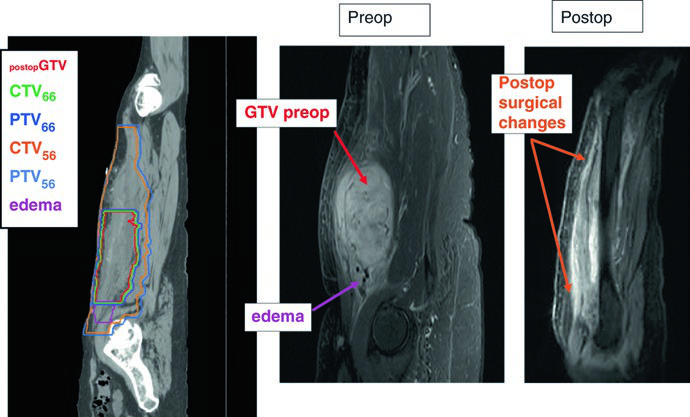

Tras la resección quirúrgica completa, no existe GTV para delinear. La estrategia cambia por completo: debemos recrear la ubicación del tumor original (GTVpostop) en el TC de planificación, utilizando imágenes preoperatorias de TC o RM como referencia. Sin este paso, la cobertura adecuada del lecho tumoral original resulta imposible.

La dosis postoperatoria estándar es de 66 Gy (60 Gy puede ser aceptable en márgenes libres y bajo grado). La técnica recomendada es el boost simultáneo integrado (SIB): el CTV66 recibe dosis alta en la región de mayor riesgo, mientras que el CTV56 cubre la zona subclínica periférica a 1,69 Gy/fracción hasta 56 Gy. Para enfermedad residual macroscópica irresecable, se emplean 70 Gy en fracciones de 2 Gy según la tolerancia regional.

| CTV56 | GTVpostop + 4 cm longitudinal y 1,5 cm radial hasta barrera anatómica. Tejidos quirúrgicos alterados, cicatrices y drenajes con margen de 1–2 cm si no están en CTV66. Edema peritumoral contorneado por separado; RM postoperatoria reciente recomendada. |

La simulación por TC con cortes de 2,0 mm es el estándar para todos los casos descritos. El corregistro con RM debe realizarse siempre que sea posible — tanto en el escenario preoperatorio como en el postoperatorio. En el postoperatorio, tanto la RM preoperatoria como la postoperatoria deben importarse y fusionarse con el TC de planificación para comprender la extensión tumoral original y los cambios quirúrgicos.